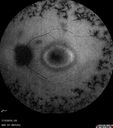

Retinitis Pigmentosa - Simplex - 16 year old female good vision428 viewsDifficulty with night vision

No family history

VA 20/25 OD, 20/16 OS

Negative for RPE65